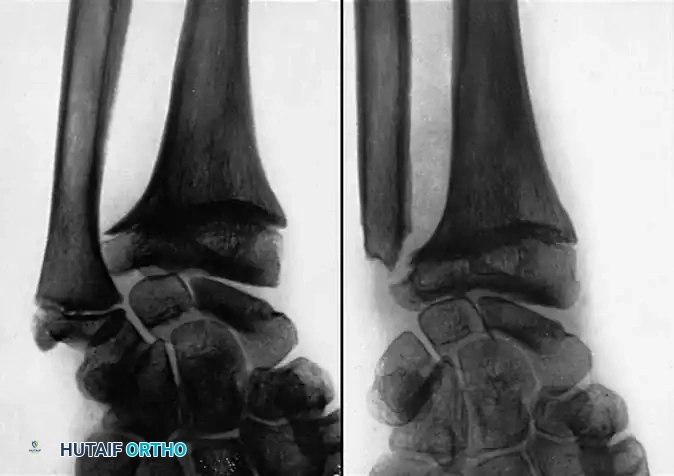

Plain anteroposterior (AP) and lateral radiographs of both wrists in neutral rotation are mandatory. The uninjured wrist serves as a critical template for surgical reconstruction.

Normal

While no absolute radiographic criteria define a "significant" malunion, several parameters correlate strongly with poor functional outcomes:

* Intraarticular Incongruity: Knirk and Jupiter, alongside Hastings and Leibovic, established that radiocarpal joint incongruity > 2 mm leads to poor results and inevitable posttraumatic arthritis.

* DRUJ Step-off: A 1 to 2 mm step-off at the DRUJ produces significant mechanical symptoms.

* Dorsal Angulation: Stockley and Porter noted that dorsal angulation > 20 degrees and radial inclination < 10 degrees cause a profound loss of grip strength.

* Sagittal Tilt: Fourrier et al. concluded that a loss of sagittal tilt of 20 to 30 degrees causes significant functional impairment.

Table 55-2: Radiographic Criteria for Acceptable Healing of Distal Radial Fractures (Graham & Hastings)

* Radioulnar length: Radial shortening of < 5 mm at DRUJ compared with contralateral wrist.

* Radial inclination: Inclination on PA film ≥ 15 degrees.

* Radial tilt: Sagittal tilt on lateral projection between 15-degree dorsal tilt and 20-degree volar tilt.

* Articular incongruity: Intraarticular step-off ≤ 2 mm at the radiocarpal joint.